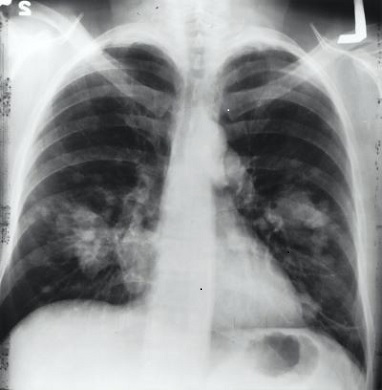

기침, 발열, 식욕부진, 기력 저하, 구토, 설사, 탈수, 두통, 인두염, 피곤함, 근육통, 발한, 청색증, 천식음, 호흡곤란, 흉막 염성 흉통, 짙은 화농성의 가래, 흉수, 빈맥, 빈호흡, 천명음, 나음, 청진 시 호흡성 수포음(crackles), 저산소증, (crackles), 저산소증, 저혈압, 촉각 진탁음(tactile fremitus)이 나타나고, 타진 시 둔감한 탁음(dullness)이 들리기도 한다. 또한 흉부 X-ray 상에서 폐렴 경결이나 다발성 경결이 나타내고 피검사에서 백혈구 수치 증가, 및 염증 수치 증가 등의 증상들이 있다.

주로 폐렴의 진단은 흉부 X-ray이며 기관지 내시경 검사, 정확한 진단으로는 폐 CT 등이 있다. 또한 입원한 환자들이 고열이 지속적으로 발생하거나 폐렴 증상 등이 호전을 보이지 않으면 가래 배양검사와 혈액 배양 검사를 나가기도 하여 균에 적절한 항생제를 쓰는데 도움을 받을 수 있다.